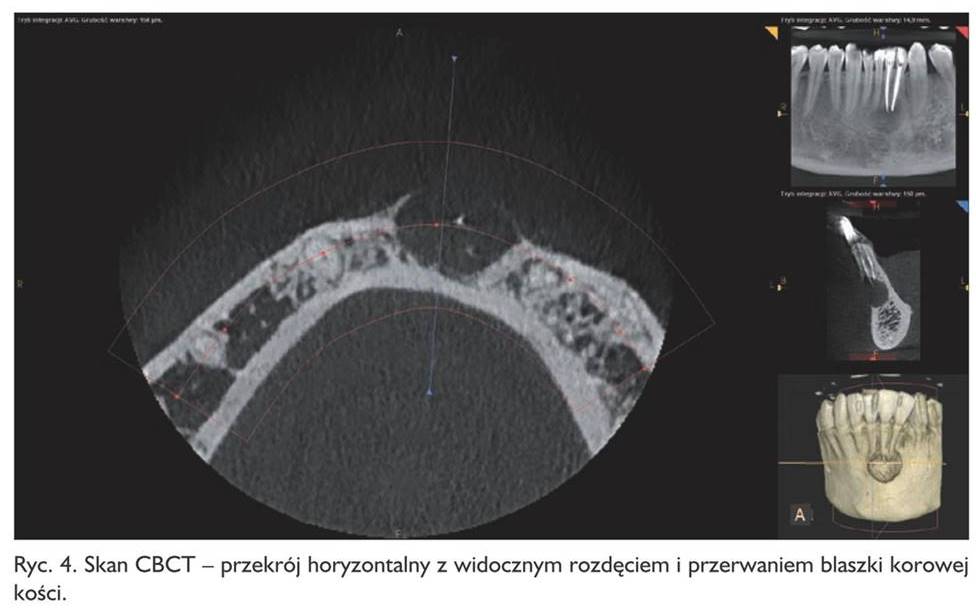

Pacjent zgłosił się ponownie dopiero po roku!, w marcu 2015 roku (pracował za granicą). Dolegliwości ustąpiły, aczkolwiek odczuwał pewne „drętwienie” tej okolicy. Zęby ponownie otwarto, wypełniono kanały metodą kondensacji bocznej gutaperki, zamknięto płynnym kompozytem oraz szkło‑jonomerem i wykonano badanie tomografii komputerowej wiązki stożkowej tej okolicy (ryc. 2, 3, 4), które ujawniło duży ubytek kostny okolicy wierzchołków korzeni zębów 32, 31, 41 z utratą blaszki wargowej części zębodołowej żuchwy, odpowiadający obrazowi torbieli korzeniowej.